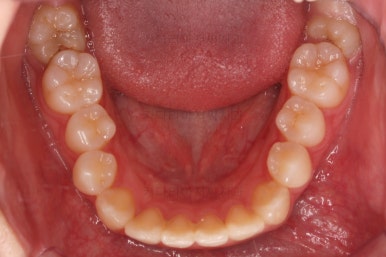

부산교정 키다리아저씨치과에 처음 내원하셨을 당시의 입안 모습과 X-ray 사진입니다.

초진 시 다른 부위들 사진입니다.

약간의 주걱턱 느낌에 약간의 돌출감, 전반적인 치열의 가지런한 느낌은 나쁘지 않았지만 약간의 불량한 교합상태였어요.

다른 부분은 크게 바꾸지 말고 약간의 교합조절과 어금니 치료에 초점을 맞춰서 교정치료 계획을 잡았습니다.